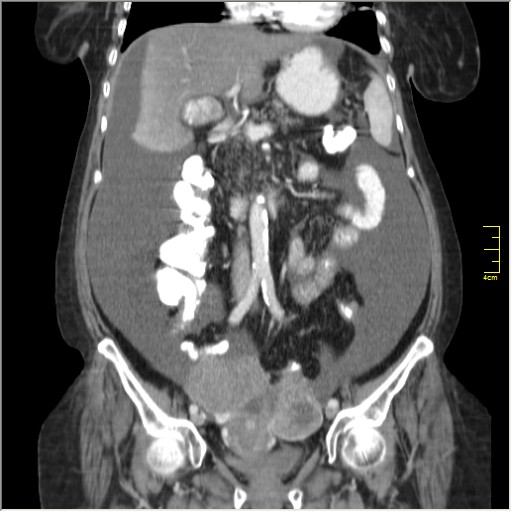

Женщина 72 года. Поступила с жалобами на вздутие живота. После осмотра хирургом, была сразу направлена на КТ брюшной полости.

Итак, асцит с объёмным образованием таза. В данном случае можно быть более конкретным, у пациентки неоплазия правого яичника с региональной лимфаденопатией (увидели?) и выраженным асцитом, характерным именно для злокачественных опухолей яичников. Пациентка оперирована ( операция Вертгейма); диагноз верифицирован: аденокарцинома правого яичника (серозная). Направлена к онкологу для дальнейшего лечения.